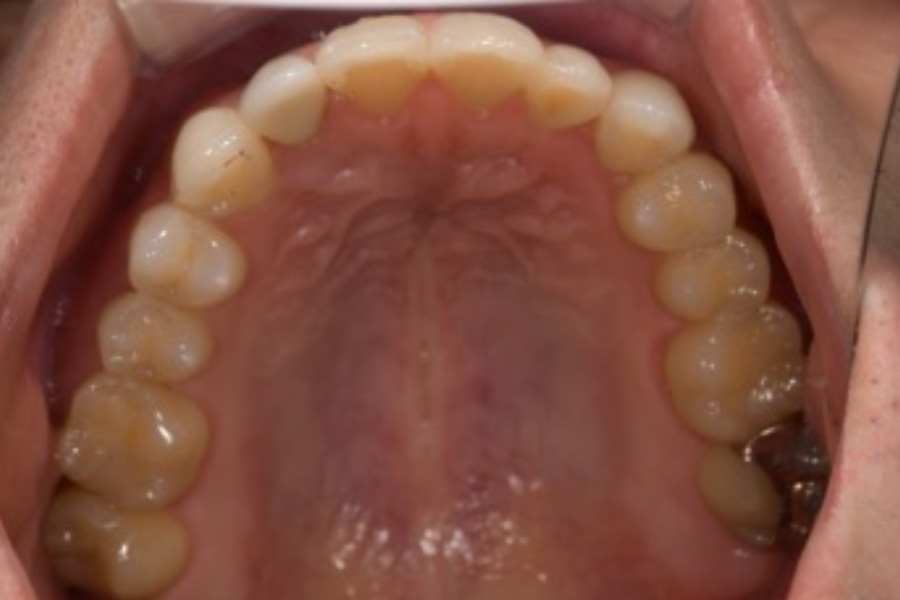

治療前

治療後

主訴 八重歯を含めた全体的なガタつき

治療内容 目立ちにくいマウスピース矯正(非抜歯矯正)

歯と歯の間に隙間をつくることにより、歯列弓を広げながら治療を行いました。